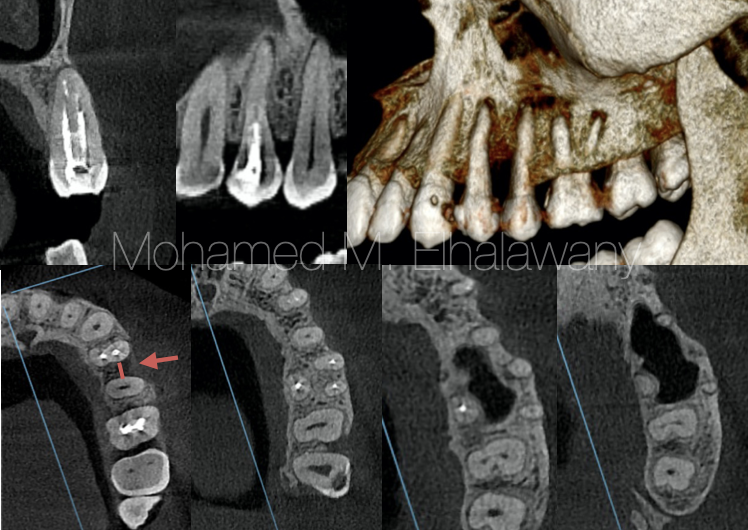

图2

图3

通过对CBCT扫描(图3)的多个不同视角(轴向、冠状、矢状和3D)的检查,发现患者在第一或第二前磨牙下没有任何类型的根尖囊肿。至于第一前磨牙(编号24),存在根尖牙周炎,这主要是因为编号24长时间没有进行根管填充。但注意到在两颗前磨牙之间存在水平骨丧失(红色箭头),这与囊肿的位置相同。

由此可见,这个囊肿并非源自牙齿或牙槽骨,可能的鉴别诊断为:牙龈囊肿。

牙齿与这种类型的囊肿形成没有关系。因此,对第一前磨牙进行根管治疗并不是一个正确的决定,这导致了大量的时间和金钱浪费,并且不幸的是,前磨牙失去了活力。所有这些问题都源于在治疗前未进行术前X光检查以进行正确诊断。